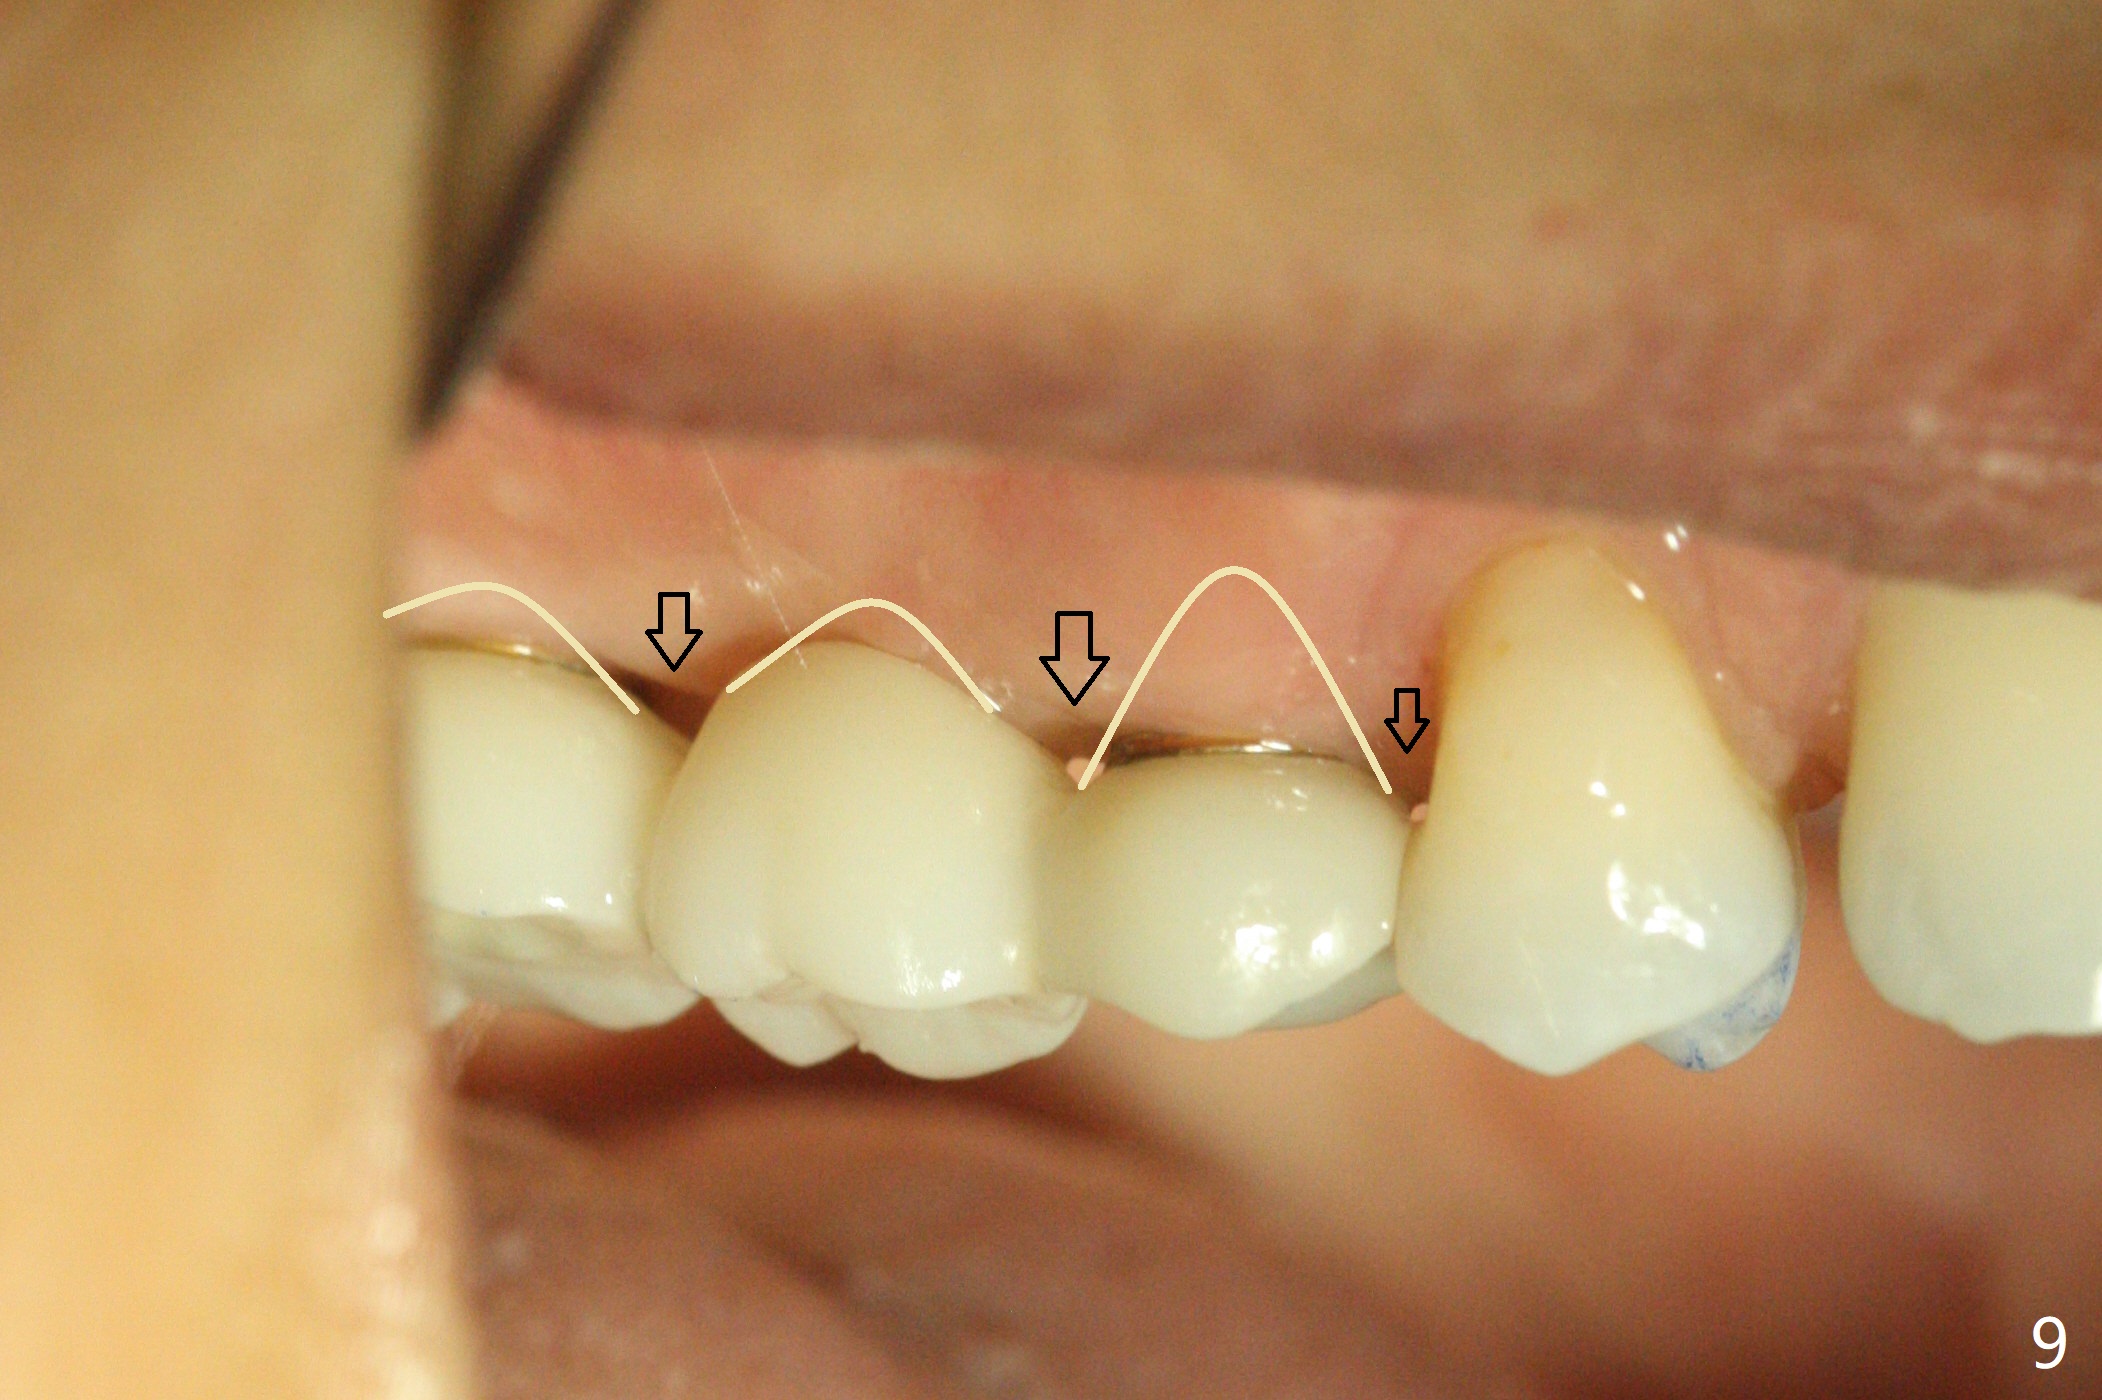

Eight months post socket preservation, the bone density at #2 feels low during osteotomy.  The site is underprep not only in depth, but also in diameter (4.0x7.3 mm with 10.5 mm offset), but a 5x7.3 mm implant is ~ 1 mm shy of the purposed depth.  Following 4.5x7.3 and 4.0x8.5 mm drills (without air leak), the implant reaches the depth, but with ~ 5 Ncm insertion torque (Fig.1).  Placement of the same sized implant at #4 (healed site) is smooth with satisfactory stability (~30 Ncm, Fig.2,3).  Ideally the site of #2 should have been prepared with sinus lift so that the apex of a longer implant would be engaged to the sinus floor for stability.  These two implants heal normally clinically and radiographically 1.5 months postop (Fig.4-6).  Bone surrounds the implant at #2 when it is uncovered 4 months postop (Fig.7).  The retainer at #4 looks short with large gingival embrasure (Fig.8 *) 6.5 months postop.  Finally the patient is ok with it because she does not like gingivectomy.  Provisional should have fabricated (Fig.9 light yellow curved lines) to create gingival scallops with secondary formation of papillae (arrows).